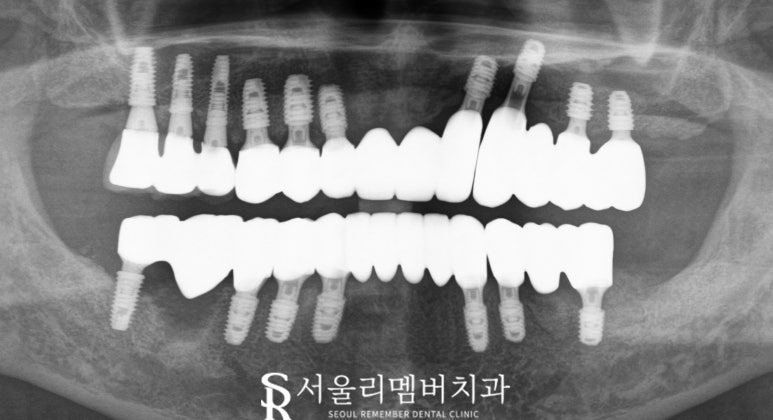

최종 임플란트 완성

술 후 환자는 안정된 상태에서

빠르게 회복하셨습니다.

잇몸도 점차 개선되었고,

무엇보다 전체 임플란트를 통해

이전에 흔들리던 치아와 통증에서

벗어날 수 있었습니다.

이후 정기검진과 관리를 통해 환자는

다시 건강한 구강 환경을 유지할 수 있게 되었습니다.